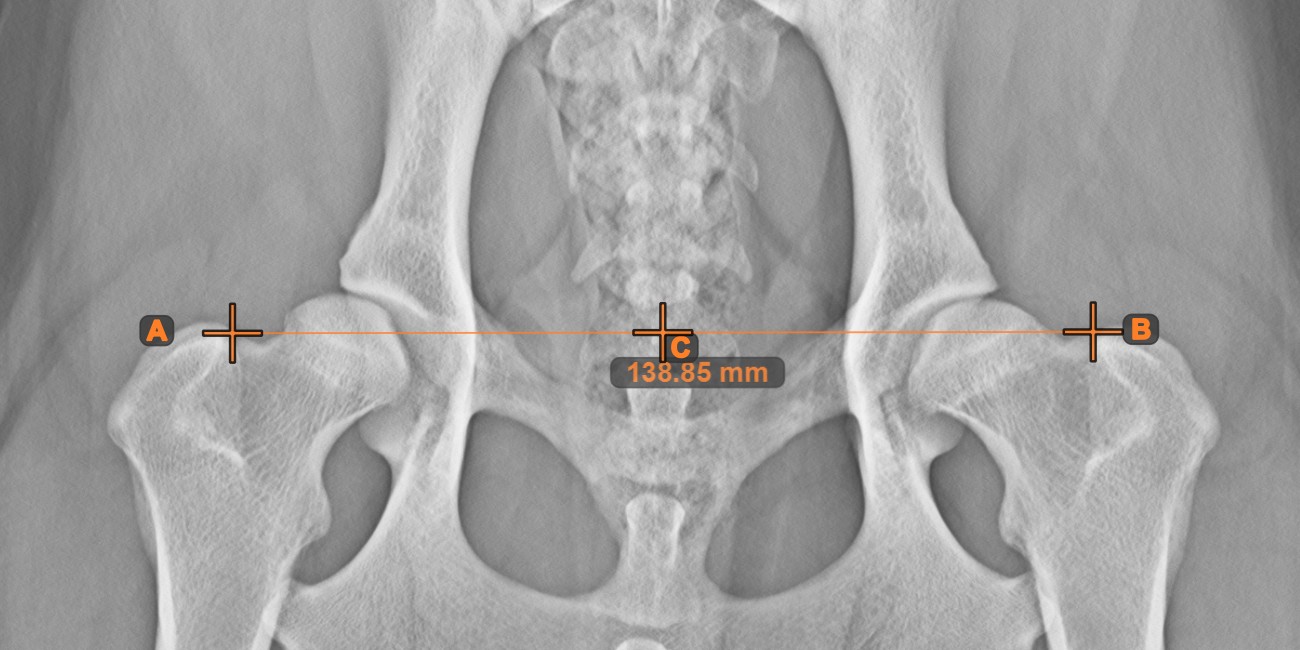

Vonal középpontja¶

Azonosítsa és jelölje meg egy új vagy meglévő vonalmérés középpontját a jelenetben a Vonal középpontja eszközzel.

Válassza ki az eszközt a bal oldali eszköztárból, és rendelje hozzá az egyik elérhető egérgombhoz. Helyezze el a kezdő- és végpontot a jelenetben, válassza ki őket a már meglévő pontok közül a képen, vagy válasszon ki egy már meglévő vonalat a jelenetből. A vonal középpontja automatikusan kiszámításra kerül és elhelyezésre kerül a jelenetben. A vonal középpontját mindig a C betű jelzi.